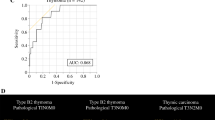

ROC curve analysis showed that a ΔSUVmax value of -25% could discriminate responders from non-responders with a sensitivity of 88% and a specificity of 80% (Fig. 2).